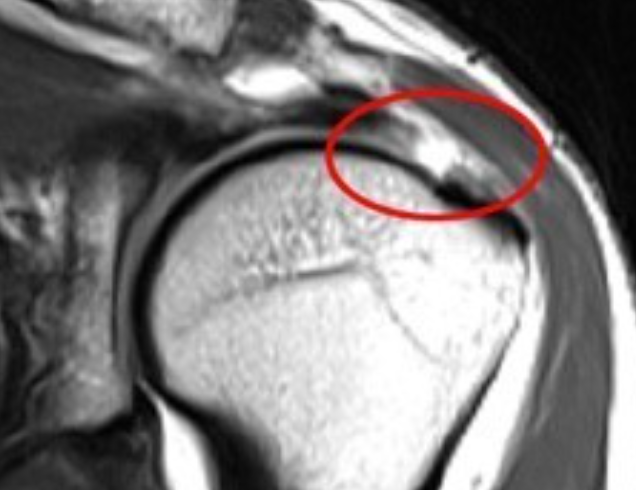

회전근개파열

이런 요인들이 복합되어 회전근개가 조금씩 찢어지면 회전근개 부분 파열이 생기고, 완전 파열에까지 이를 수 있습니다.